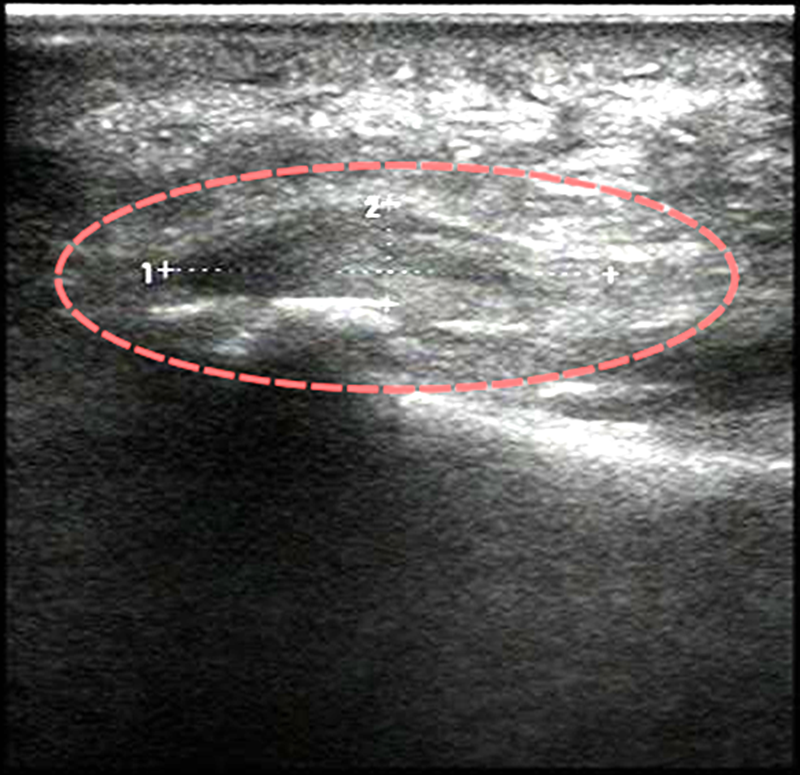

医生通过肌骨超声确诊该患者为足底筋膜炎,存在筋膜增厚、水肿的情况,无骨刺问题,并据此为其制定了专属治疗方案。

2.中度:如上述患者,采用超声引导下注射治疗,微创操作可实现精准止痛,同时配合专业按摩、佩戴足底支撑垫,一般1-2个疗程即可明显缓解症状;